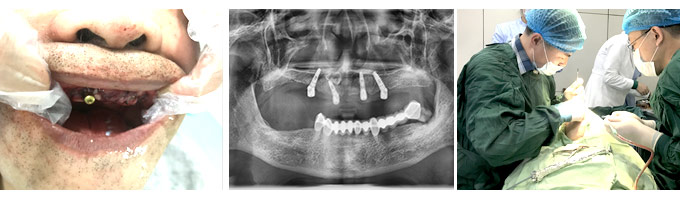

今年国庆节恰逢遇到中秋节,为了迎接双节的来临,沈阳康贝佳口腔特邀请了北京种植博士吴高谊莅临沈阳亲诊(10月1日-3日)。吴博士从事口腔治疗40余年,是国内“All-on-4技术”口腔种植医生,有着丰富的口腔种植经验,特别擅长半/全口和疑难种植。这次吴博士来到沈阳康贝佳,预约到他种牙的人可有福了。

来自沈河区、今年70岁、已经“三顾吴高谊”的程老先生,吴博士刚到院就接待了他。在仔细查看了程老的口腔CT片后,吴博士通过电脑为程老量身定制了种牙方案。不一会儿,就通过微创即刻种植技术为程老种上了好牙。“之前观看过吴医生的三场种植牙手术直播,对吴博士的技术很放心!结果真的一点感觉都没有,牙椅还没躺热呢,6颗牙就种好了!”看着镜子里自己又重新“长”出来的牙,程老感慨自己可以乐享晚年口福。>>>我也要种牙,马上咨询